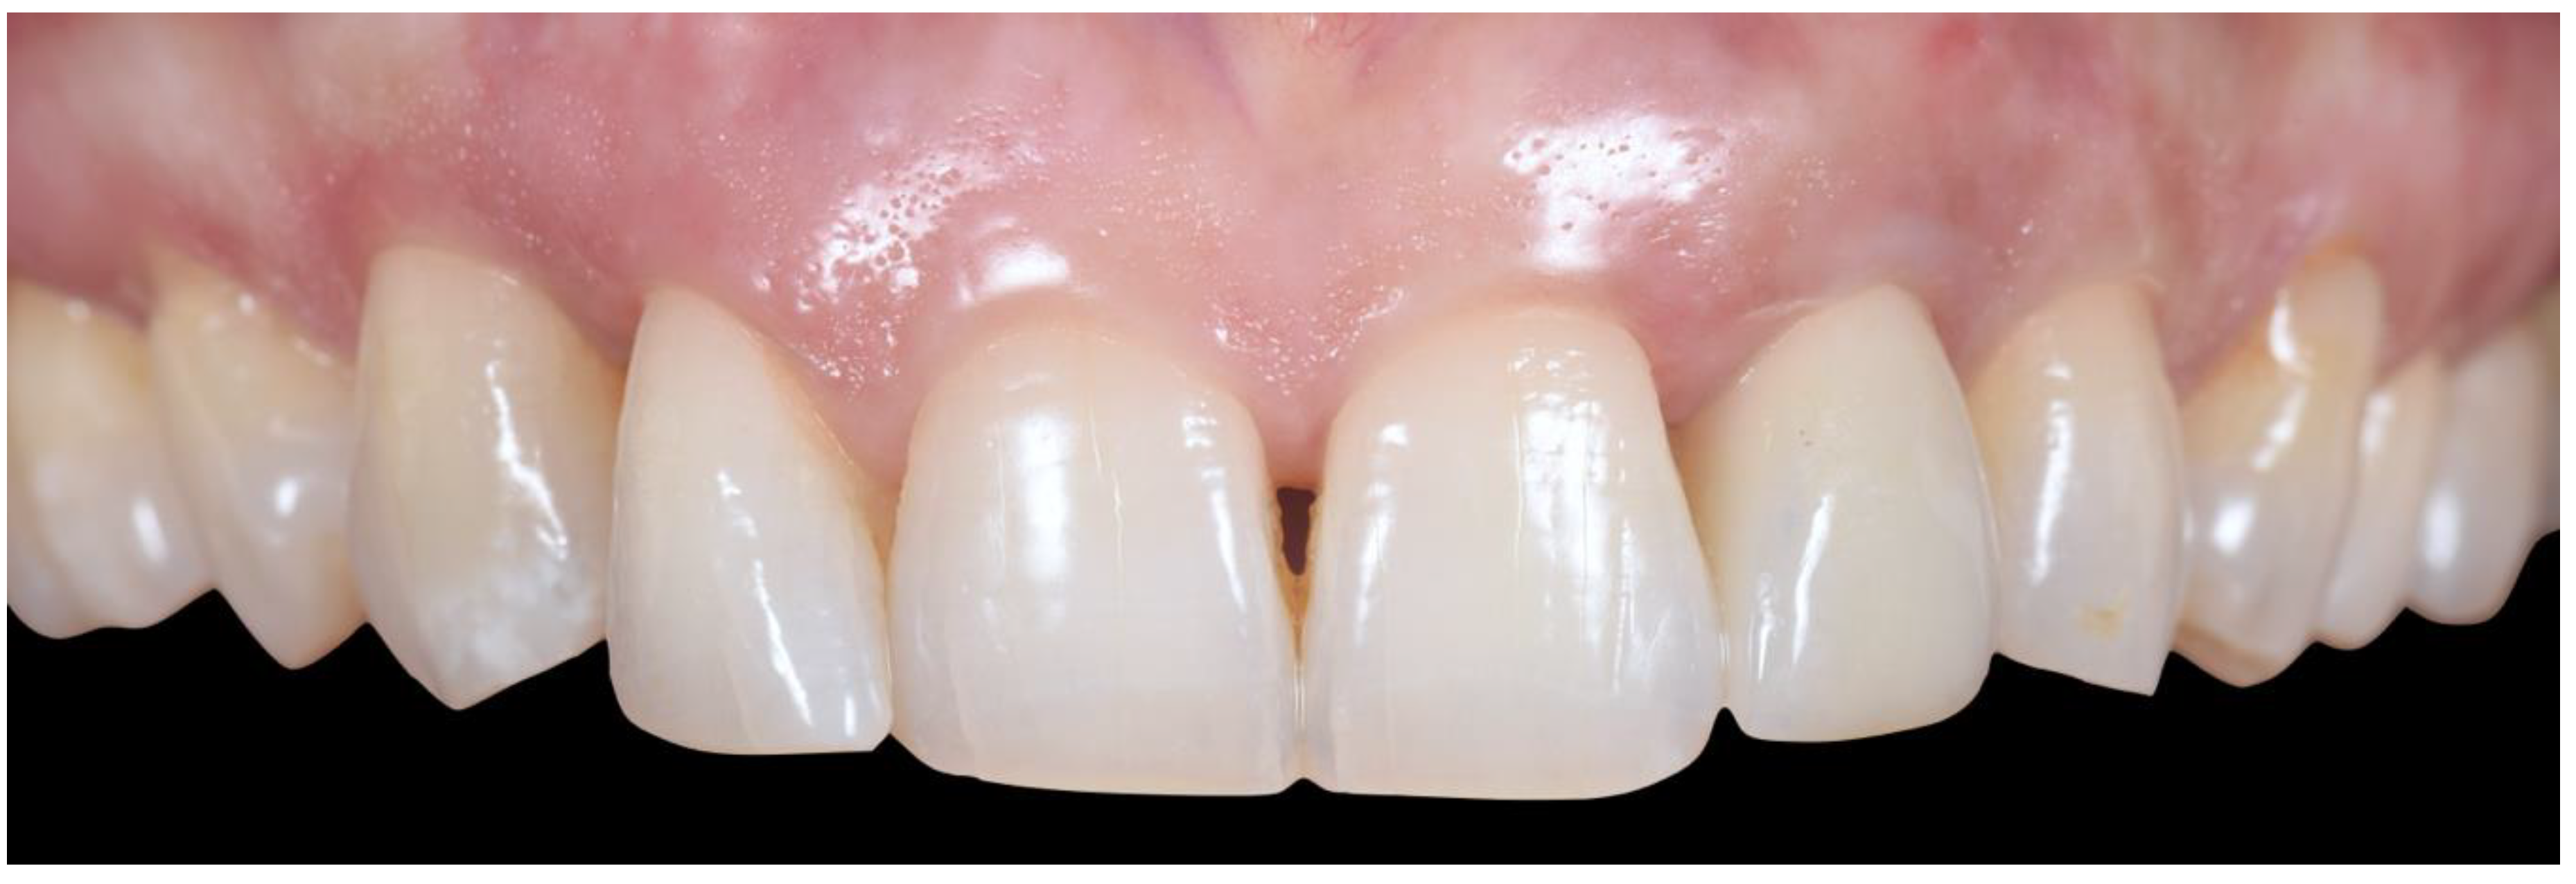

2.4. Transitional Restoration Stage

2.5. Impression Stage

2.6. Lab Stage

2.7. Prosthesis Delivery